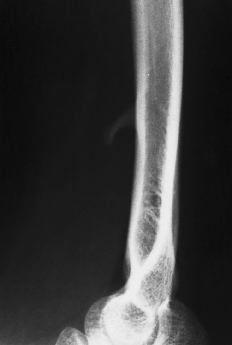

Mediante un acceso medial se alcanzó a la zona por el lado posteromedial del músculo bíceps. Se pudo observar la presencia de una prominencia ósea con un refuerzo fibroso que se dirigía desde la punta de la misma hacia la epitróclea, correspondiendo al denominado ligamento de Struthers (Fig. 2); algunas fibras musculares del pronador redondo se insertaban en la zona más distal de la apófisis. Tras la exposición de la apófisis se apreció su forma de gancho, con una base amplia y de unos 2 cm de longitud, situada en la cara anteromedial del húmero, que se dirigía hacia abajo, adelante y medialmente. En contacto con su cara interna (cubital) se distinguía el nervio mediano y, más medialmente, la arteria humeral, sin que ninguna de estas estructuras presentara alteraciones. No se evidenció ninguna estructura neurovascular en la zona lateral (radial) de la apófisis. Tras la disección anatómica, nerviosa y vascular se procedió a la resección de la exóstosis mediante escoplo, tallando un cajeado de la base de implantación en el húmero (Fig. 3). El período postoperatorio transcurrió sin alteraciones y a los 12 días se retiró el vendaje y los puntos. En la revisión a los 6 meses la paciente estaba asintomática y sin evidenciar signos de recidiva en la radiografía.

Figura 2. Imagen previa a la resección de la apófisis donde se observa el ligamento de Struthers (flecha).